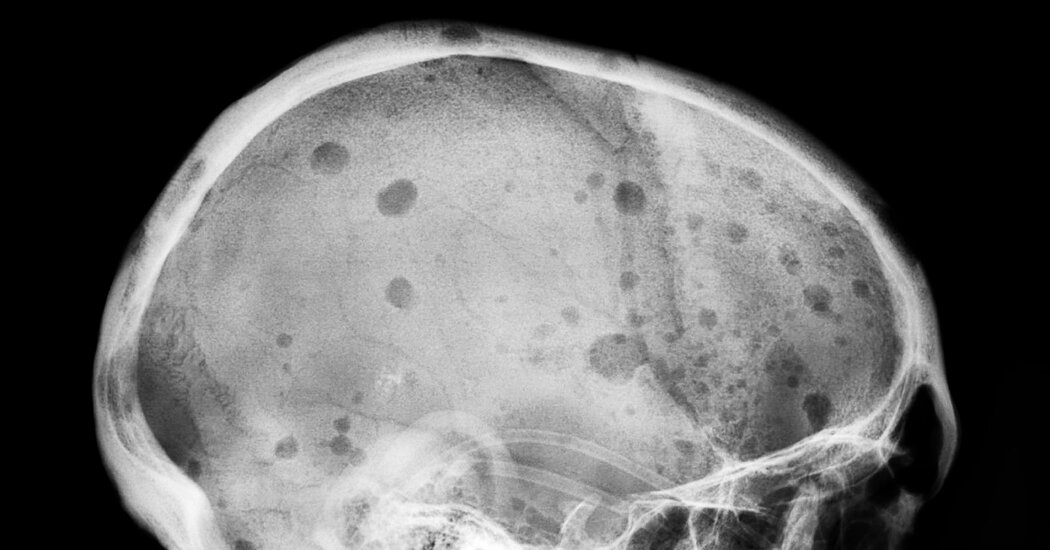

A 28-year-old new mom began experiencing unusual neck pain and itching after drinking wine, initially blamed on hormones. When a neck lump appeared, doctors scanned her and diagnosed stage 2 Hodgkin lymphoma in 2025. She has since started chemotherapy and is focused on her two sons as she undergoes treatment.